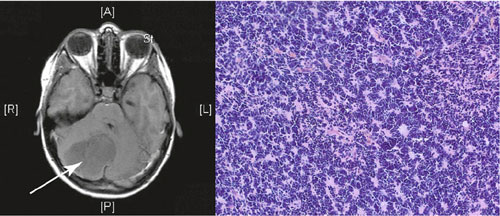

Magnetresonanztomografie (links, der Pfeil deutet auf den Tumor) und Gewebeschnitt

(rechts) eines Medulloblastoms

Ja, besonders dringend brauchen wir neue, zielgerichtete und schonende Therapieverfahren. Die pädiatrischen Hirntumoren sind die häufigste Krebserkrankung im Kindesalter, die einen tödlichen Verlauf hat. Die Behandlung der Tumoren und die damit verbundenen Nebenwirkungen sind oft sehr belastend für die Kinder und können das heranwachsende Gehirn in seiner Entwicklung beeinträchtigen. Wir beschränken uns in unseren Untersuchungen auf die beiden häufigsten kindlichen Hirntumoren, das Medulloblastom und das pilozytische Astrozytom. In Deutschland sind jedes Jahr etwa 300 Kinder von diesen Hirntumoren betroffen.